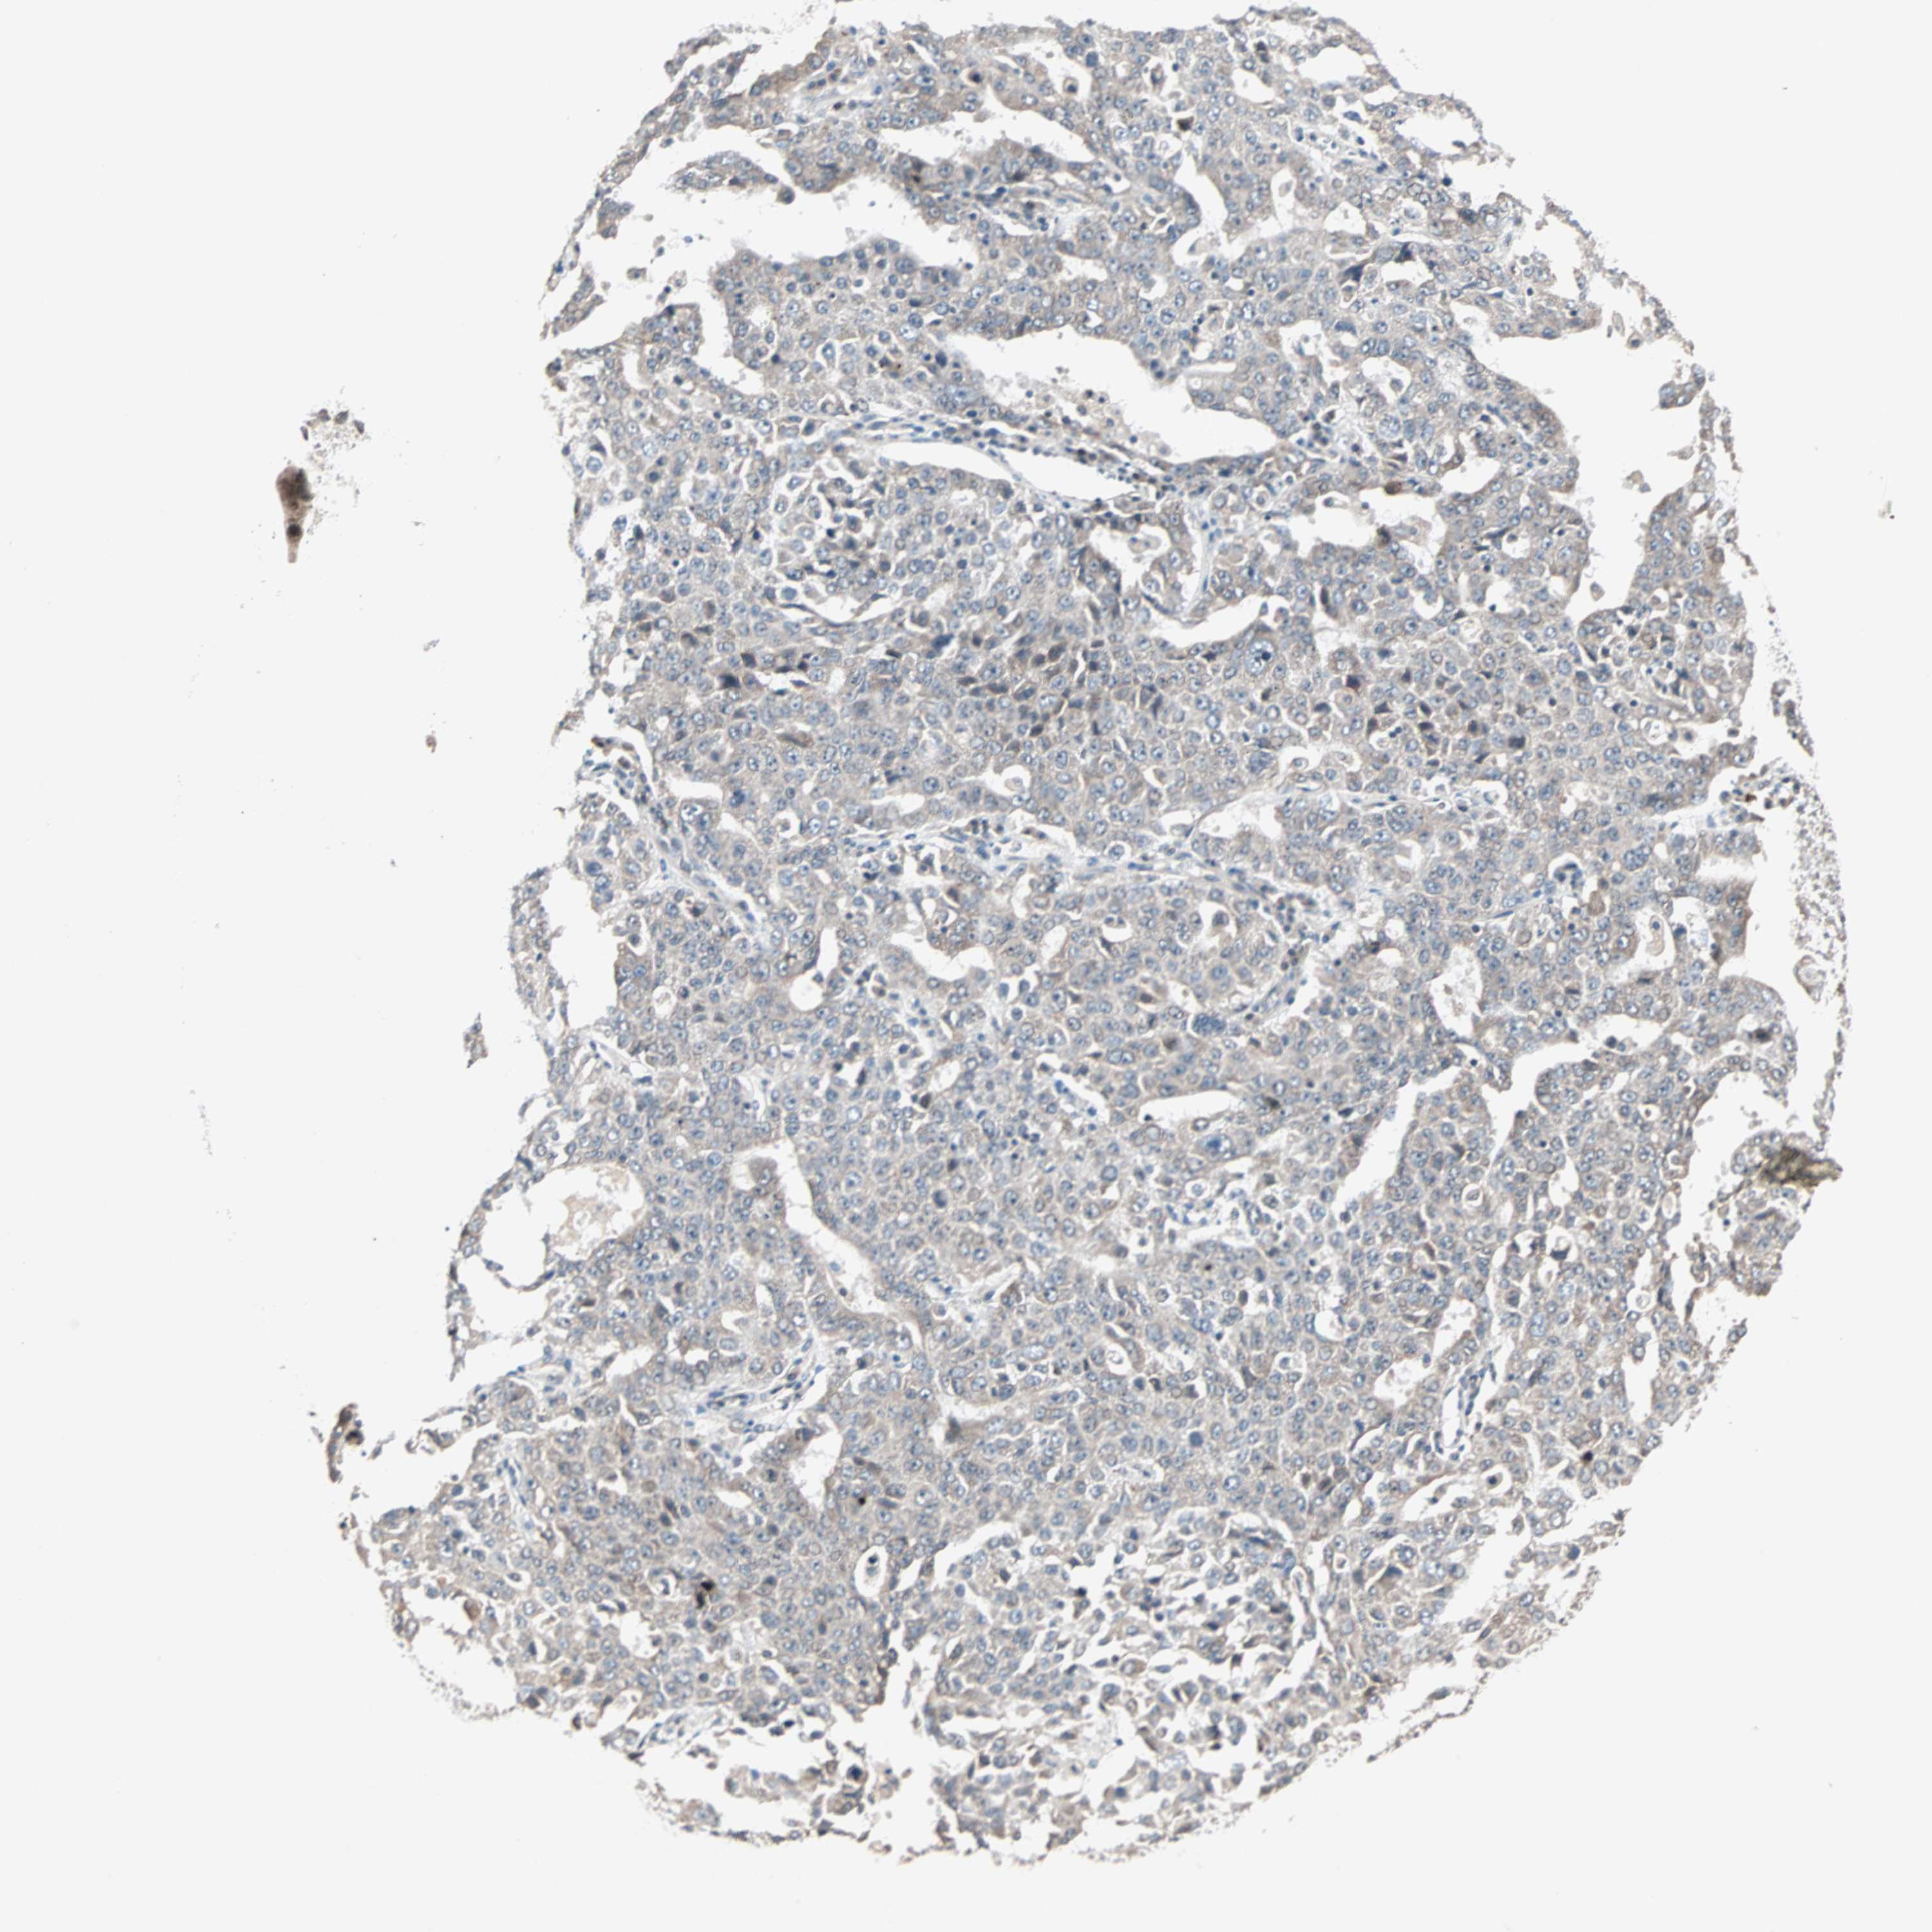

OVARIAN CANCER - Protein expressioni

A mouse-over function shows sample information and annotation data. Click on an image to view it in a full screen mode. Samples can be filtered based on level of antibody staining by selecting one or several of the following categories: high, medium, low and not detected. The assay and annotation is described here.

Note that samples used for immunohistochemistry by the Human Protein Atlas do not correspond to samples in the TCGA dataset.

Antibody stainingi

Antibody staining in the annotated cell types in the current human tissue is reported as not detected, low, medium, or high, based on conventional immunohistochemistry profiling in selected tissues. This score is based on the combination of the staining intensity and fraction of stained cells.

Each image is clickable and will lead to virtual microscopy that enables deeper exploration of all samples and also displays staining intensity scores, fraction scores and subcellular localization as well as patient and tissue information for each sample.

Antibody HPA007267

Staining

High

Medium

Low

Not detected

Intensity

Strong

Moderate

Weak

Negative

Quantity

>75%

75%-25%

<25%

None

Location

Nuclear

Cytoplasmic/membranous

Cytoplasmic/membranous,nuclear

Cystadenocarcinoma, serous, NOS

Carcinoma, endometroid

Cystadenocarcinoma, mucinous, NOS

Carcinoma, NOS